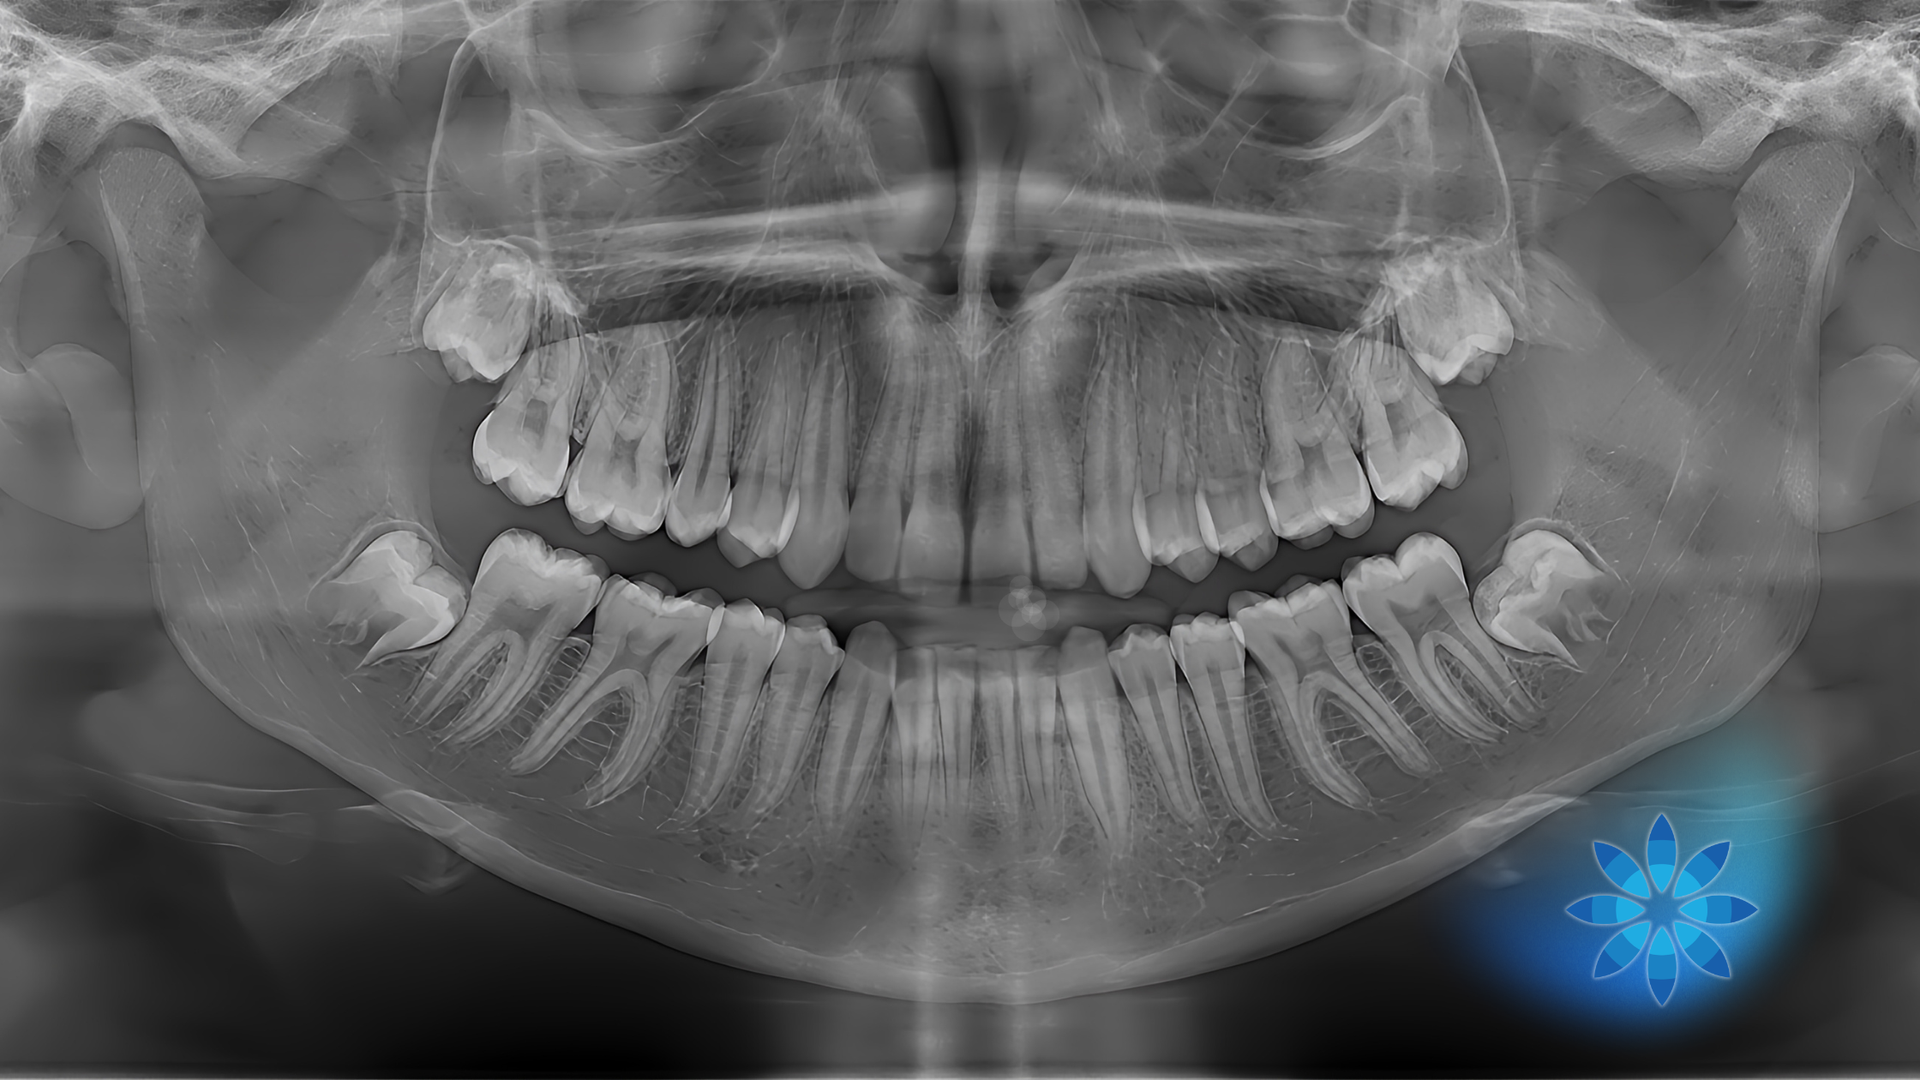

Jaw clicking typically occurs in the temporomandibular joint (TMJ), which connects your jawbone to your skull. This joint plays a crucial role in everyday movements like talking, chewing, and yawning. A clicking or popping sound can happen when the joint or surrounding structures move slightly out of alignment during motion. For some people, it’s occasional and painless. For others, it may be accompanied by tension, stiffness, or discomfort.